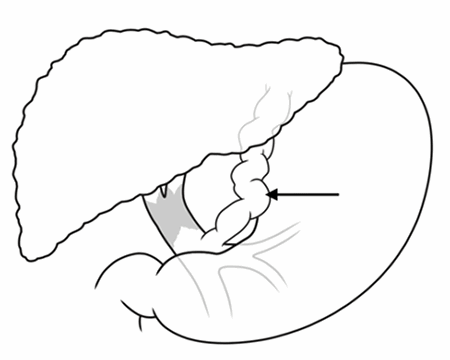

Figure 4. Illustration Depicting the End-To-Side Left Gastric-Portal Vein Anastomosis. Published with Permission

In this case, we report our surgical technique of using the left gastric vein as an inflow for the transplanted liver. We demonstrate that this technique is safe and feasible, even in high MELD score patients with previous extensive surgeries. Adequate preoperative testing is essential to assess the feasibility of this technique. Preoperative imaging with a CT scan to demonstrate a left gastric vein of at least 10 mm in diameter is critical. Additionally, ultrasound measured left gastric vein flow of at least 10 cm/sec should be ensured preoperatively. Small graft size is also preferable since expected flow in the left gastric vein may be lower than the native portal vein. Intraoperative assessment of graft portal flow is essential to avoid portal hypo-perfusion; in the event that portal flow is <0.5ml/gm liver, we recommend ligation of the left gastric vein distal to the left gastric to portal end-to-side anastomosis to increase the flow to the graft.